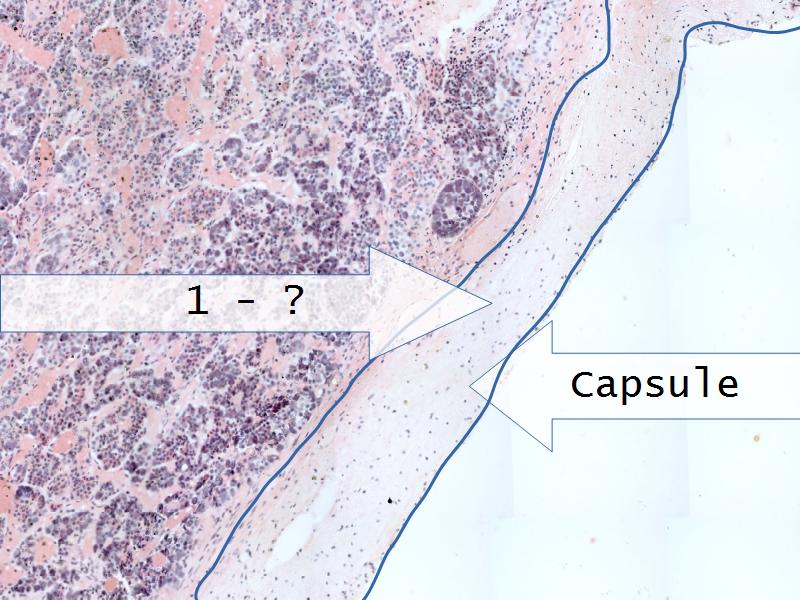

Adrenal glands

Capsule

Cortex - how many zones?

Medulla